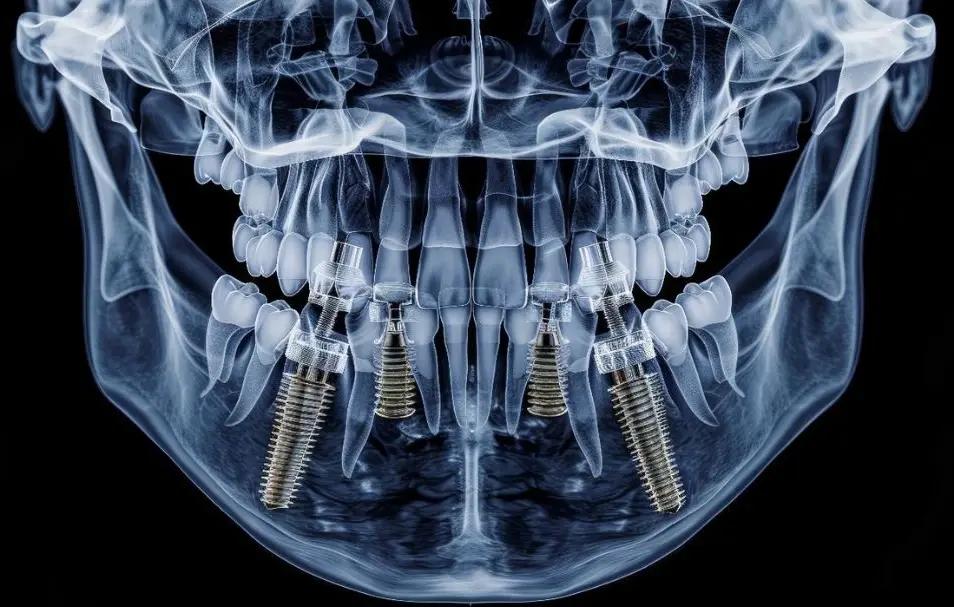

The procedure is effectively a bio-mechanical feat. A dentist is not just placing a tooth; a medical device is being placed that must fuse perfectly with living bone. This process, called osseointegration, is why cheap materials cannot be used. If the body rejects the metal, the entire procedure fails.

- High-Quality Materials: Implants are typically made from biocompatible materials like titanium or zirconia. These are chosen for their durability and ability to integrate with bone without causing an immune response. Titanium is a precious metal in the medical world, and its processing into a sterile, thread-calibrated screw is a high-cost manufacturing feat. For example, the raw material cost for a single medical-grade titanium implant screw can range from £100 to £300 before any processing.

- Advanced Surgical Expertise: Placing a dental implant requires a highly skilled dentist with specialized training in oral surgery. This expertise represents years of postgraduate education. Many implantologists have spent tens of thousands of pounds on Master's degrees just to learn how to place these screws without hitting nerves or sinus cavities. A significant portion of the fee (e.g., 35-40%) covers the surgeon's skill and time.

- State-of-the-Art Technology: Modern practices use 3D CT scanners (CBCT) to map the jaw. These machines can cost over £50,000 to buy, and that cost is factored into treatment. Digital impressions and surgical guides also ensure the screw goes in at the exact millimetre required. This diagnostic and planning technology typically accounts for 10-15% of the overall cost.

- Titanium Alloys (Mid-Price): This is the industry standard. It has been used for decades because bone loves to grow around it. It is strong, lightweight, and rarely causes reactions. Most people will have this option as it balances cost and performance. A standard titanium implant from a reputable brand costs the clinic approximately £150-£350 per unit.

- Zirconia / Ceramic (High-Price): This is often considered the "luxury" option. It is 100% metal-free and white in colour. It is often used for patients with thin gums where a metal screw might show through as a grey shadow, or for those with specific metal allergies. It is much harder to manufacture and more prone to fracture if not handled by an expert, hence the higher price. Zirconia implants can cost the clinic upwards of £400-£600 per unit.